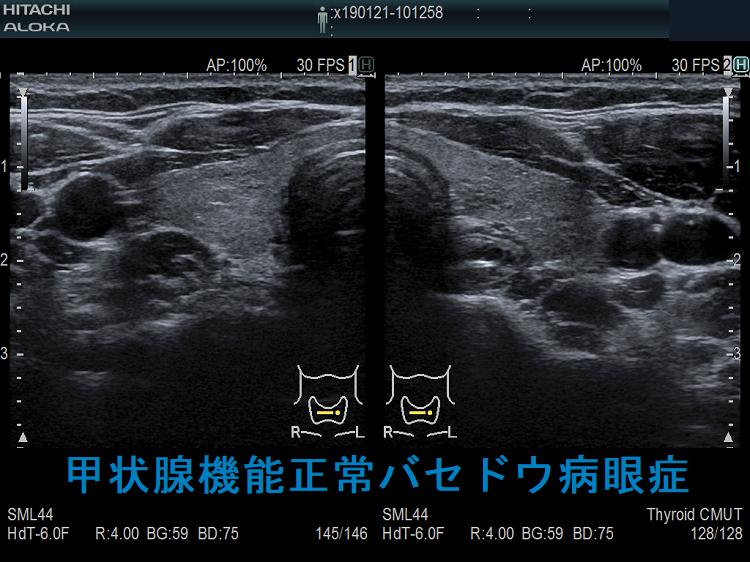

長崎甲状腺クリニック(大阪)では、メルカゾール(5mg)0.5T/日投与により数年間、甲状腺機能正常を維持している安定したバセドウ病患者にいきなり遅延型バセドウ病眼症が起こりました。そのMRI画像がこれです。

同じく、甲状腺亜全摘出20年後発症した遅延型バセドウ病眼症もありました。